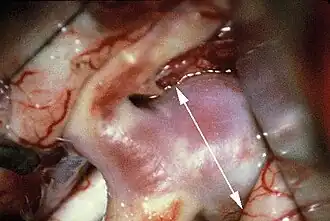

Es haben sich das Clipping und das Coiling bewährt. Die Methodenwahl hängt neben der Verfügbarkeit vor allem von den spezifischen Gegebenheiten des jeweiligen Aneurysmas (Erreichbarkeit, Form, Weite des Aneurysmahalses, Ursprung von Gefäßen) ab:

- Clipping (Verschluss durch eine Klemme) des Aneurysmas als neurochirurgischer Eingriff, um ein Nachbluten zu unterbinden

Beide Methoden, Clipping oder Coiling, erfolgen für gewöhnlich in den ersten 72 Stunden nach Blutung oder erst 10 Tage später, da die Gefäße in der Zwischenzeit besonders empfindlich reagieren und die Entwicklung von Gefäßspasmen wahrscheinlich ist.

Die chirurgische Therapie ist mit hoher Evidenz zur Prophylaxe von Rezidivblutungen geeignet.[7]

Das Coiling bietet den Vorteil, dass man für den Patienten schonender zu den betroffenen Gefäßstellen vordringen kann, ohne dass, abhängig von der Lage des Aneurysmas, der Schädel eröffnet und Hirngewebe verletzt oder entfernt werden muss. Es ist auch zur Prophylaxe von asymptomatischen Aneurysmen geeignet.